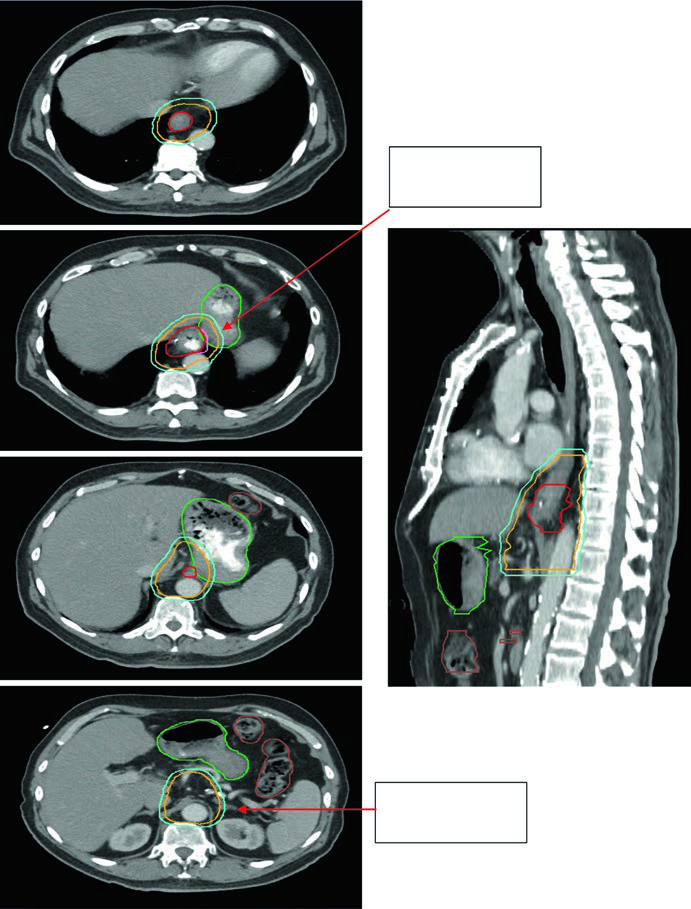

Case 3: GEJ Adenocarcinoma — 75-Year-Old, uT3N0

A 75-year-old patient with GEJ adenocarcinoma uT3N0. Contours demonstrate CTV extension into the proximal stomach with coverage to the celiac axis. Delineated volumes: stomach (dark green), large bowel (brown), esophageal GTV (red), CTV (orange), PTV 50.4 Gy (cyan). Celiac axis coverage is mandatory for distal and GEJ tumors.

Case 4: GEJ Adenocarcinoma — 59-Year-Old, uT3N2

A 59-year-old patient with GEJ adenocarcinoma uT3N2. PET showed FDG-avid paraesophageal nodes and primary located 36–40 cm from the incisors. The sagittal planning CT shows the ITV reflecting GTV movement, with CTV covering 3–4 cm above the ITV. Volumes: stomach/duodenum (dark green), nodal GTV (light green), esophageal GTV (red), ITV (pink), CTV (orange), PTV 50.4 Gy (cyan). Paraesophageal lymph nodes were included in the treatment field.